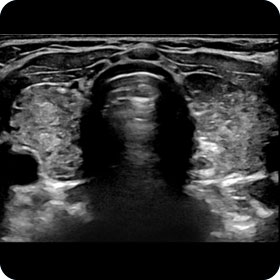

Wirbelsäule

| Konventionelles Röntgen | Fraktur, Degenerationen |

| CT | Fraktur |

| MRI | Bandscheibenpathologien, Nervenwurzeln, Frakturalter, Spondylodiszitis |

Myelon

| CT | Keine |

| MRI | Myelopathie, demylelinisierende Erkrankung |